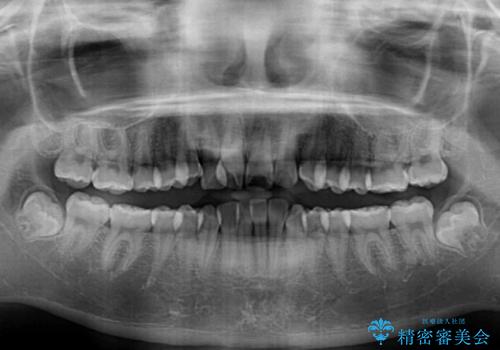

- 歯のデコボコや八重歯、クロスバイトを気にして来院された患者様です。

上下左右第一小臼歯4本を抜歯し、ワイヤー装置にて歯列を整え、さらには少しでも口元を引っ込めるよう矯正治療を行うこととしました。